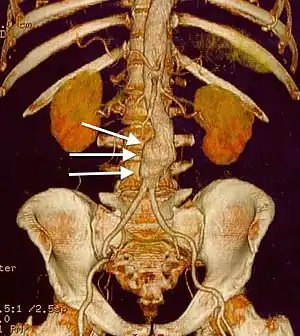

![]() | |

| CT reconstruction image of an abdominal aortic aneurysm (white arrows) | |